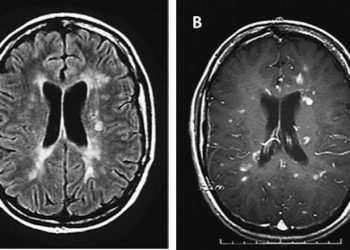

ЧИТАТЬ ВСЕИстория болезни 35-летний мужчина, с известным случаем гепатита С, имел измененный уровень сознания и снижение зрения. Он был жизненно стабилен с...